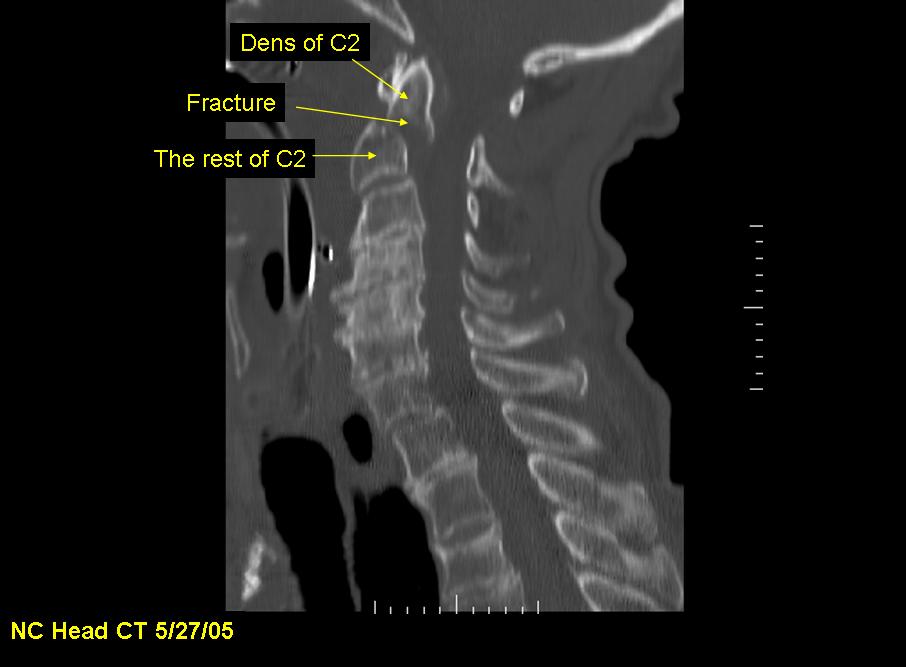

X-ray, CT, and MRI image studies at the hospital show C1 and C2 fractures with spinal cord injury, resulting in quadriplegia. T2-T4 spinous processes and several left ribs are also fractured. The patient never regains consciousness and dies the next day.

The dens, also called the odontoid process, is the portion of the C2 (the "axis") about which the C1 and the head rotate. Because the dens extends superiorly into the ring of C1, it is subjected to shear forces and fracture from C1 in neck injuries. The dens can then impact the spinal cord, injuring or severing it. In this case, although the patient's spinal cord was not severed, impact from the dens caused a spinal cord hematoma resulting in quadriplegia.